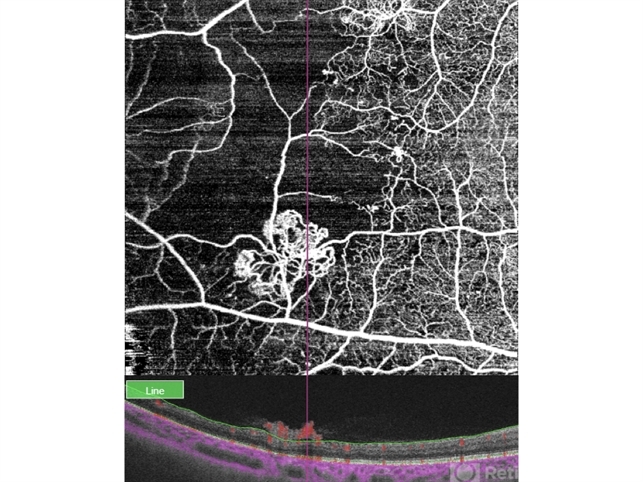

- PDR, neovascularization (NV), OCT, OCT Angiography

Optical coherence tomography system

Topcon Triton Plus - Description

- OCT and OCTa of a diabetic patient with severe PDR, showing the anatomical location and blood flow of neovessels